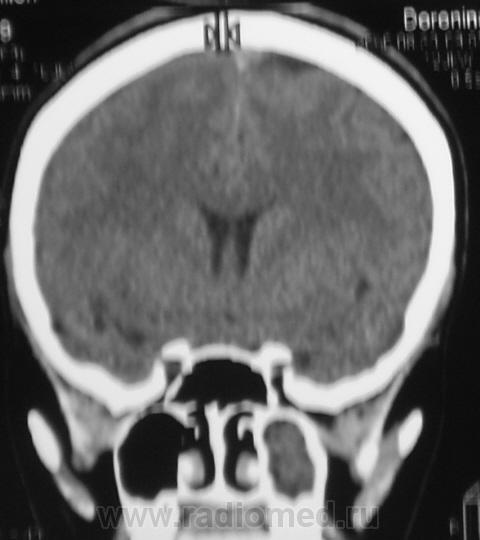

ППН.   Клиника гайморита.

Все-таки, гаймароэтмоидит: имеется содержимое в левых клетках решетчатого лабиринта. А почему одонтогенный? Зубы внедрены в пазухи с обеих сторон, оценить состояние периапикальных мягких тканей слева из-за жидкости не предсталяется возможным.